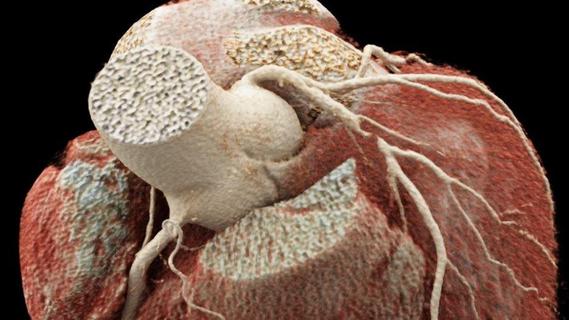

Wie funktioniert der Herzschrittmacher?

Das Gerät, etwa so groß und schwer wie zwei aufeinanderliegende Zwei-Euro-Münzen, wird über einen Hautschnitt unterhalb des Schlüsselbeins eingesetzt. Von diesem Aggregat führen Elektroden (Sonden) durch eine Vene in die Herzkammer oder Vorkammer. Diese Sonden – je nach Bedarf und Zusatzfunktionen eine, zwei oder auch drei – regen das Herz elektrisch zum Schlagen an, wenn es Störungen gibt.